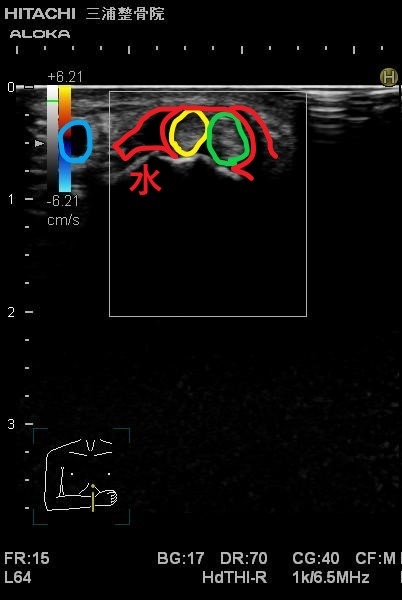

エコーではこのように写ります。

エコーの良い所として

動かしながらも観れるので

関節がどのくらいぐらついているかなども

判断できます。